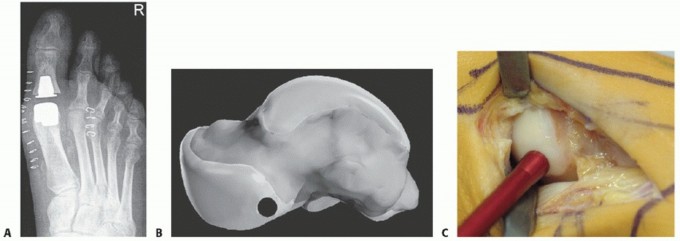

FIG 2 • A. Postoperative radiograph of first MTP joint prosthesis. B,C. Osteochondral autograft transplantation from the plantar medial talus.*

A contraindication for cheilectomy with microfracture is the stiff joint of types 3 and 4 osteoarthritis. In this case, in patients with a low activity level who want good ROM, a resurfacingtype prosthesis (not a “head resection” type) is a good alternative and is being used with increasing frequency (FIG 2A).

Patients with isolated, painful osteochondral lesions without degenerative joint disease may be considered in rare cases for microfracture alone (for a small, contained lesion) or for an osteochondral transplantation from the plantar medial talus (FIG 2B,C).